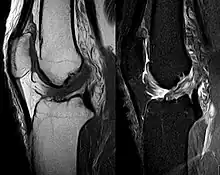

RMN-ul arată semnal normal al ambelor ligamente încrucișate (săgeți)